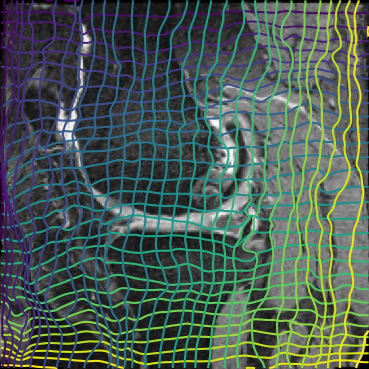

Inverse consistent rigid, affine, nonparametric, and MLP registration. We train networks on MNIST 5s using the methods in Secs. 3 and 4, demonstrating that the resulting networks are inverse-consistent. Our TwoStepConsistent (TSC) operator can be used on any combination of the networks defined in Sec. 3. For demonstrations, we join an MLP registration network to a vector field registration network, and join two affine networks to two vector field networks. Fig. 2 shows successful inverse-consistent sample registrations.

| Moving Image | Warped Image | Fixed Image | Moving Image | Warped Image | Fixed Image |